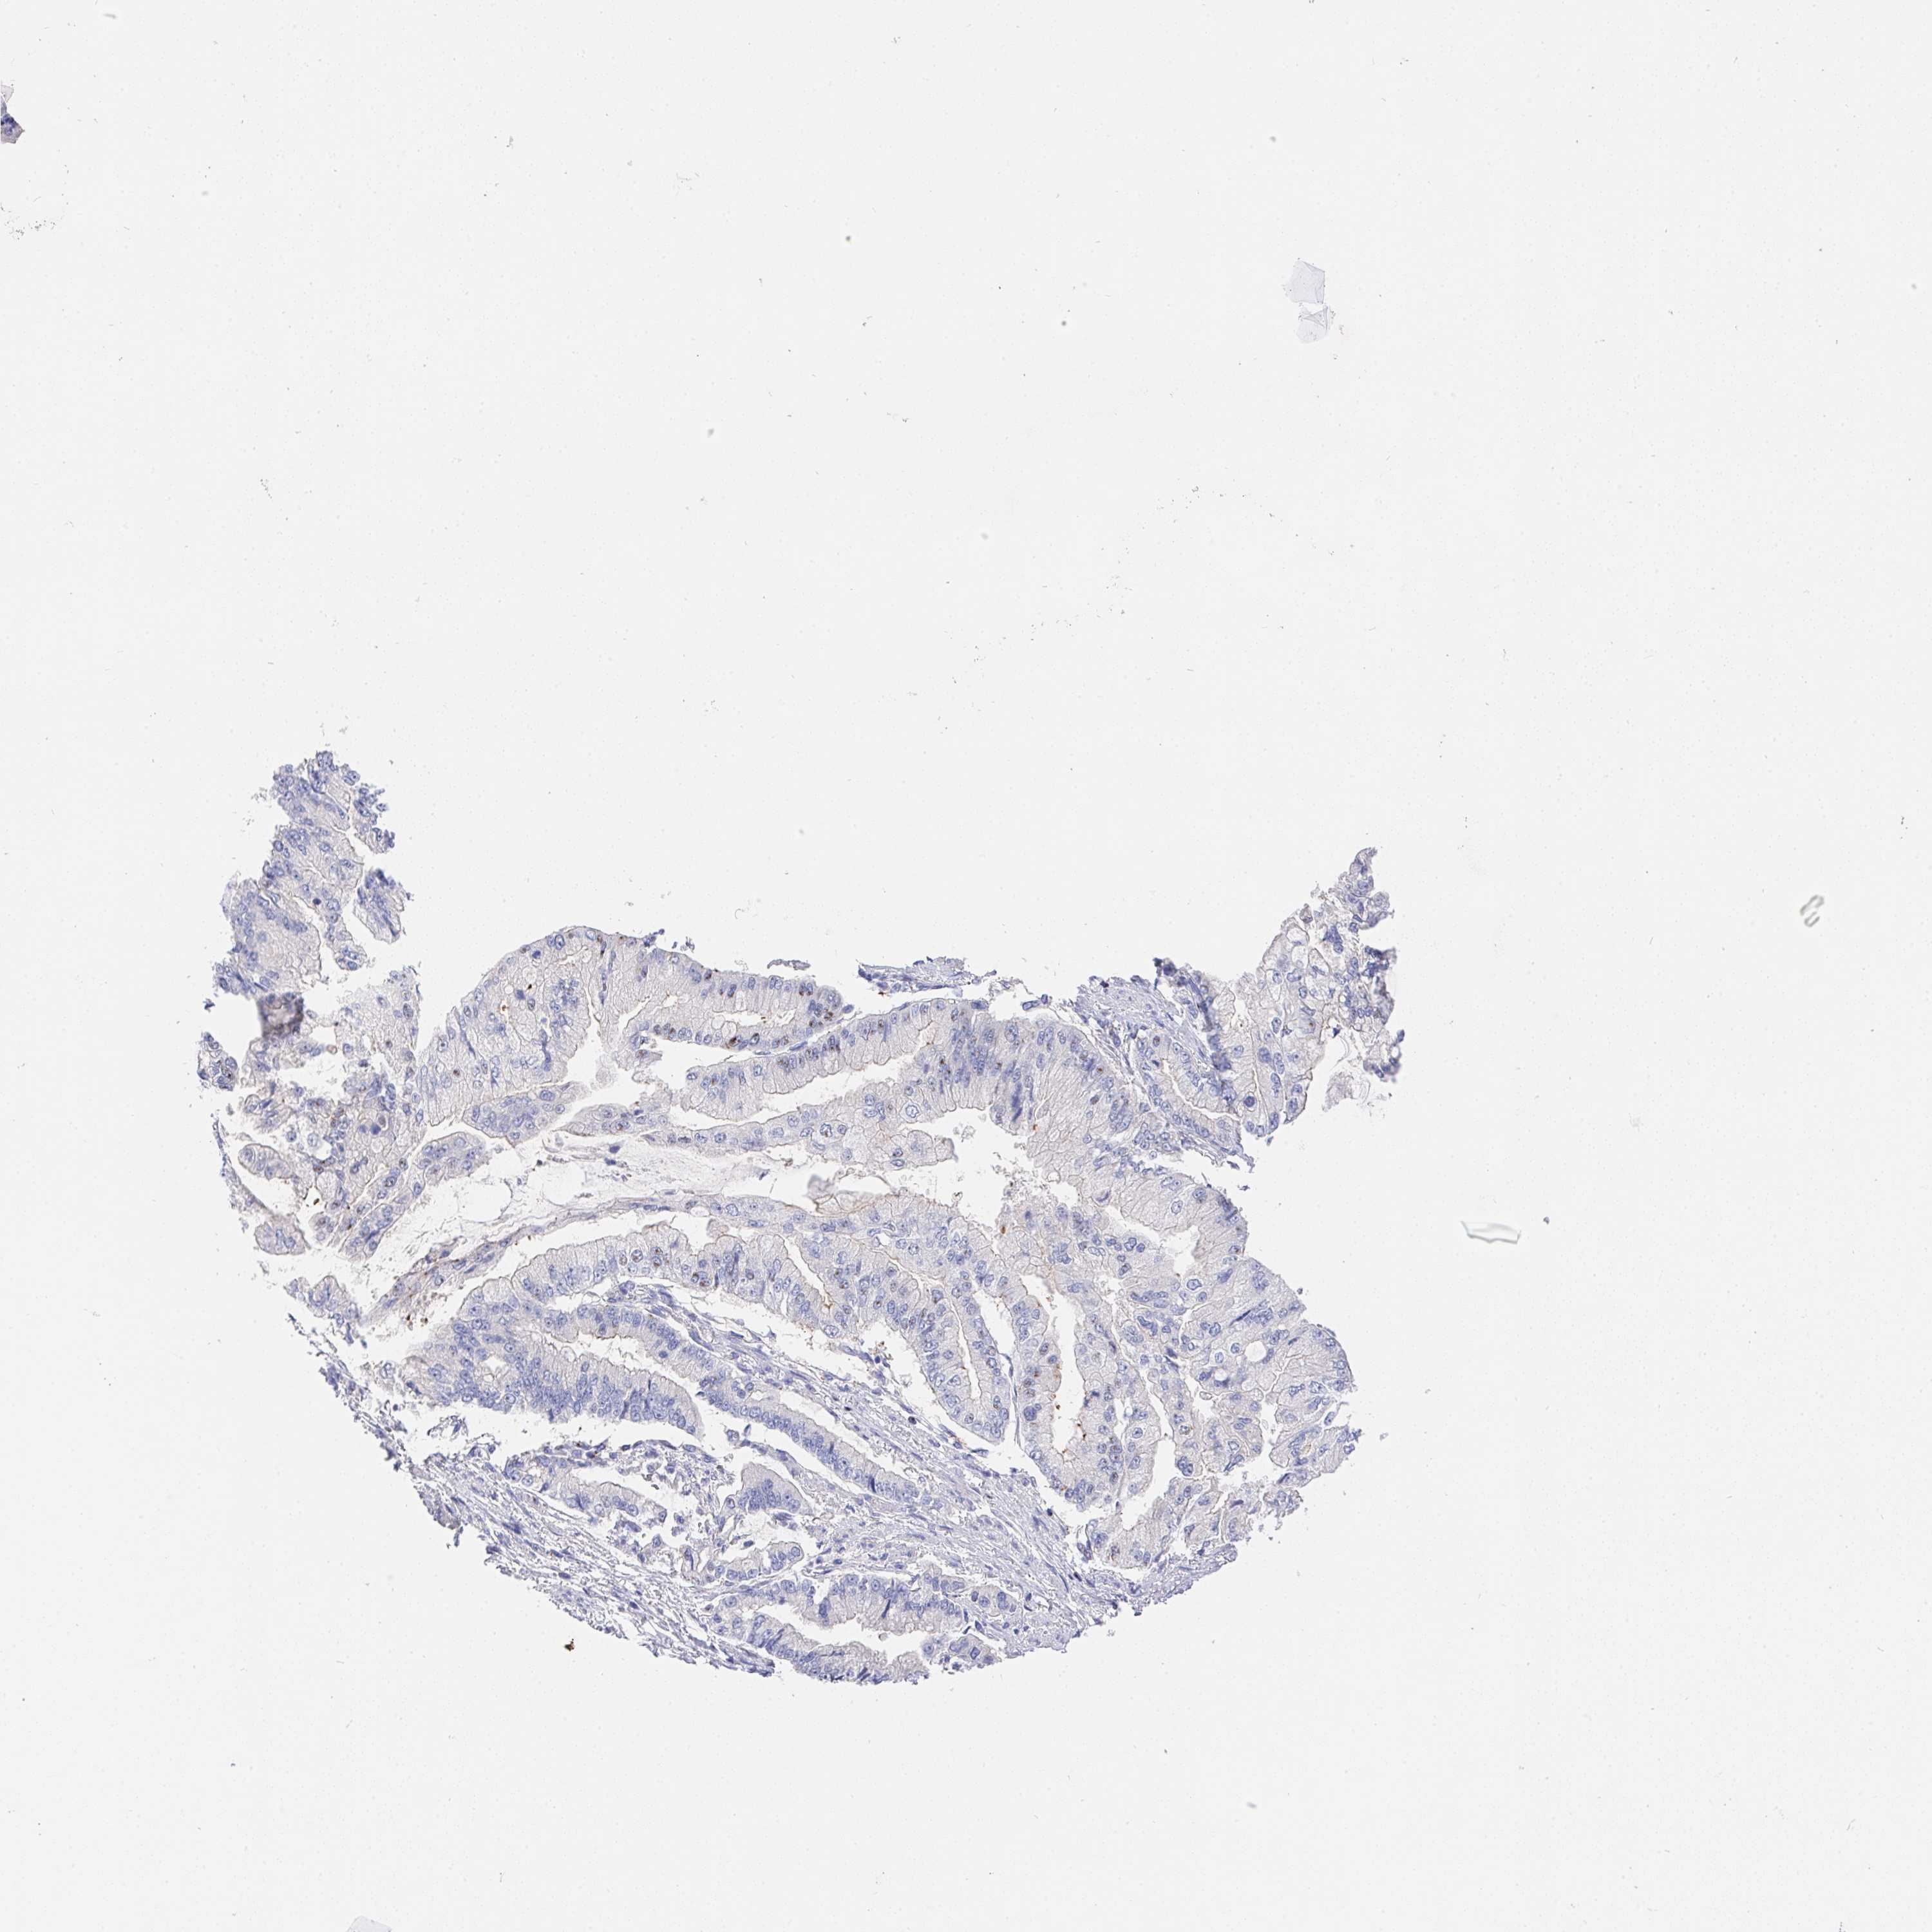

STOMACH CANCER - Protein expressioni

A mouse-over function shows sample information and annotation data. Click on an image to view it in a full screen mode. Samples can be filtered based on level of antibody staining by selecting one or several of the following categories: high, medium, low and not detected. The assay and annotation is described here.

Note that samples used for immunohistochemistry by the Human Protein Atlas do not correspond to samples in the TCGA dataset.

Antibody stainingi

Antibody staining in the annotated cell types in the current human tissue is reported as not detected, low, medium, or high, based on conventional immunohistochemistry profiling in selected tissues. This score is based on the combination of the staining intensity and fraction of stained cells.

Each image is clickable and will lead to virtual microscopy that enables deeper exploration of all samples and also displays staining intensity scores, fraction scores and subcellular localization as well as patient and tissue information for each sample.

Antibody HPA064183

Staining

High

Medium

Low

Not detected

Intensity

Strong

Moderate

Weak

Negative

Quantity

>75%

75%-25%

<25%

None

Location

Nuclear

Cytoplasmic/membranous

Cytoplasmic/membranous,nuclear

Adenocarcinoma, NOS